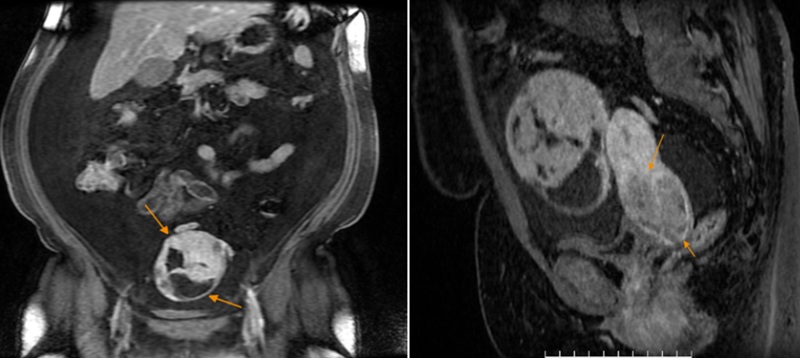

Người phụ nữ ở Hà Nội có biểu hiện chướng bụng khoảng 01 tháng gần đây nên đến Phòng khám Đa khoa MEDLATEC Tây Hồ thăm khám. Nhờ làm xét nghiệm và chẩn đoán hình ảnh phù hợp, bệnh nhân phát hiện ra dấu hiệu ung thư buồng trứng và tư vấn kịp thời để có hướng xử trí phù hợp.